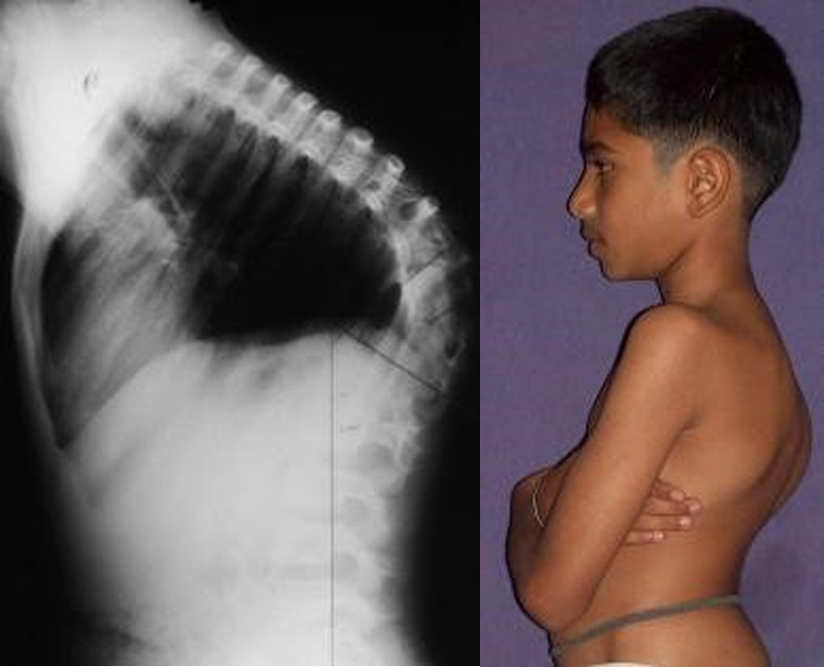

Case 2: Congenital Kyphoscoliosis at the Thoracolumbar Junction

Patient: Bharat Age: 13Y/M

Condition: Congenital Kyphoscoliosis at the thoracolumbar junction (74° kyphosis, 30° scoliosis)

Bharat’s spinal deformity was both severe and rigid due to malformed vertebrae. Instead of performing a long-segment fusion — which could have limited his spine mobility — Dr. Pithwa performed a targeted spinal osteotomy at the apex of the deformity. This innovative method corrected the deformity without unnecessarily spanning additional spinal segments, thereby preserving flexibility and long-term function.

Post-surgery, Bharat’s deformity reduced to just 30°, with a significant improvement in posture, spinal balance, and confidence. This case stands as an example of how advanced spinal deformity correction in India can achieve world-class results while maintaining motion and quality of life.